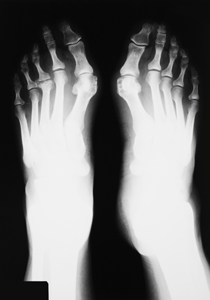

Odata cu aparitia pantofilor cu toc si a cresterii incidentei obezitatii, din ce in ce mai multe persoane au inceput sa observe formarea monturilor. Afla ce sunt monturile si cum le poti preveni sau trata.Ce sunt monturile?Monturile reprezinta deplasarea primului metatarsian spre interiorul piciorului, devenind proeminent, in timp ce degetul mare se deplaseaza catre lateral, cu deformarile aferente. Acest tip de deformari pot aparea si la nivelul celorlalte degete, in special la degetul mic. |

![]() |